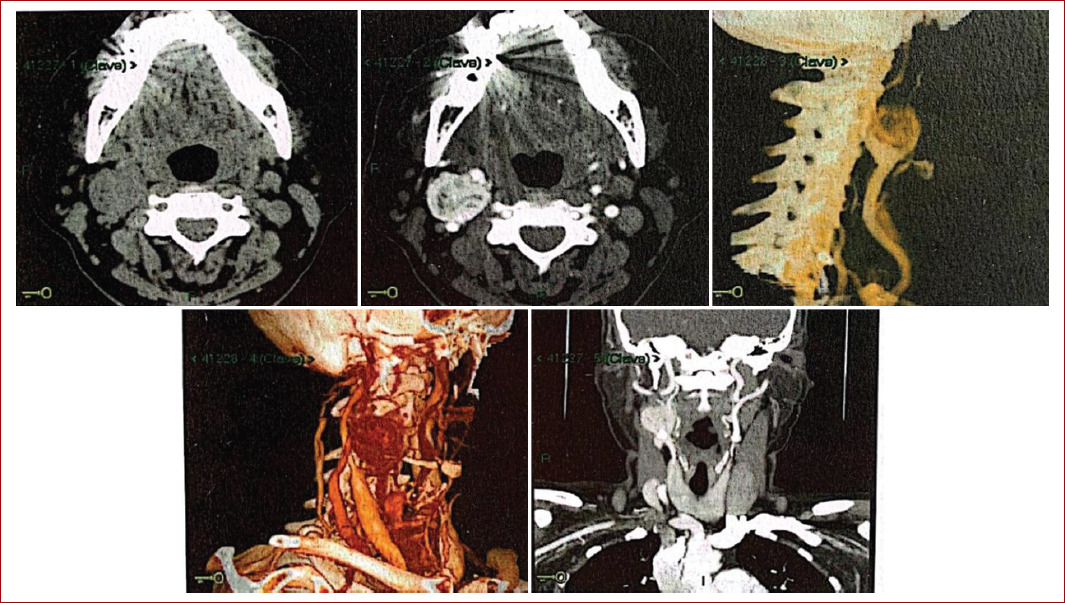

Inicia su padecimiento con un aumento de volumen de 1 año de evolución en la región del hemicuello derecho. Se realiza ultrasonido Doppler el día 16/10/2021, que reporta un tumor a nivel de la bifurcación de las carótidas de 4.69 × 2.7 × 4.446. La angiotomografía muestra un tumor en el hemicuello derecho a nivel de la bifurcación carotídea que invade las arterias carótidas externas y parcialmente las internas, de 34 × 35 mm, con realce al medio de contraste.

Inicia su padecimiento con disfagia a sólidos que progresa a líquidos. Se desconoce el tiempo de evolución, por lo que acude a valoración y se sugiere la realización de una angiotomografía, en la cual se observa un tumor en la bifurcación carotídea con realce del medio de contraste, de 34 × 28 mm, que envuelve parcialmente ambas carótidas, provocando efecto de compresión en la vena yugular interna (Fig. 3).

Figura 3 Angiotomografía en la que se observa un glomus carotídeo derecho, de aproximadamente 29 × 28 × 27 mm, con densidad semejante al músculo, separando la carótida interna de la externa.

Inicia su padecimiento en mayo de 2020, cuando se palpa un tumor en el hemicuello derecho, blando, no doloroso, por lo que acude a otorrinolaringología, donde se descarta patología de oído y se solicita ultrasonido, que reporta un tumor (no se dispone del reporte). Es derivada a unidad médico familiar y de ahí a angiología. Acude a la consulta y se le solicita una angiotomografía de cuello, la cual reporta un tumor de 29 × 28 × 27 mm, de bordes bien definidos y lisos, con densidad semejante al músculo, con dos calcificaciones posteroinferiores. Separa las carótidas interna y externa, anterior a glándula submandibular, lateral al músculo esternocleidomastoideo, con áreas hipodensas en su interior y paraganglioma carotídeo derecho.